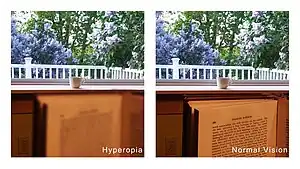

| Symptoms | Close objects appear blurry[2] |

Far-sightedness, also known as hypermetropia, is a condition of the eye in which light is focused behind, instead of on, the retina.[2] This results in close objects appearing blurry, while far objects may appear normal.[2] As the condition worsens, objects at all distances may be blurry.[2] Other symptoms may include headaches and eye strain.[2] People may also experience accommodative dysfunction, binocular dysfunction, amblyopia, and strabismus.[3]

The signs and symptoms of far-sightedness are blurry vision, headaches, and eye strain.[2] The common symptom is eye strain. Difficulty seeing with both eyes (binocular vision) may occur, as well as difficulty with depth perception.[1]